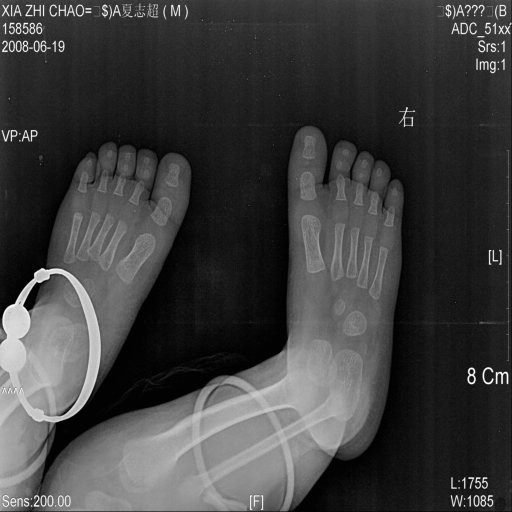

男性,22月,不能独立行走,双足外观无明显异常

双足正位未见明显异常。

骨质没见异常,还是检查脑部发育情况.